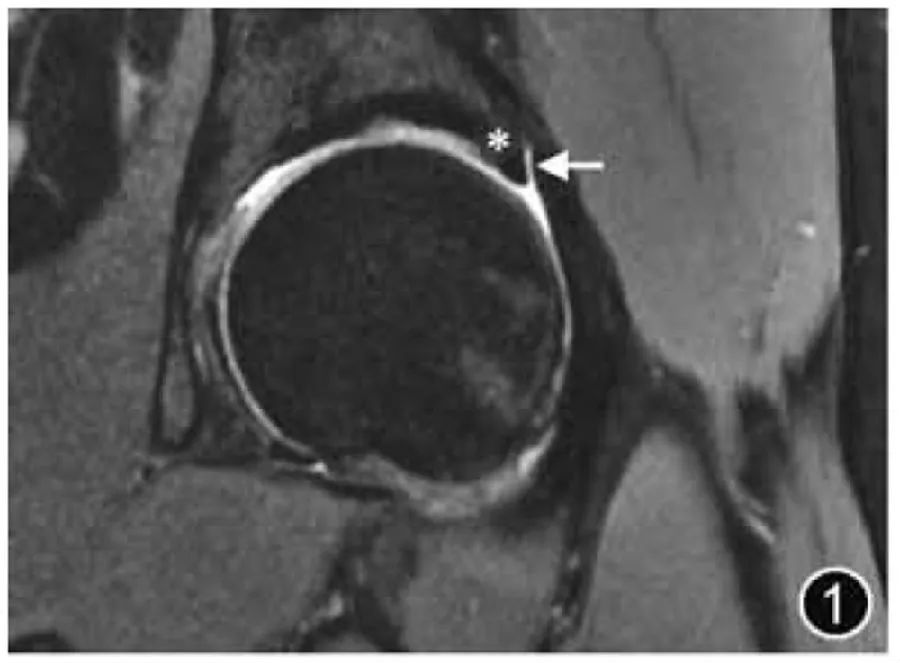

2024-05-30

Усвоили ли вы ключевые моменты МРТ-диагностики поражений тазобедренного сустава?

Для пациентов с симптомами тазобедренного сустава МРТ имеет большое значение для ранней диагностики и лечения. Она м···

узнать больше